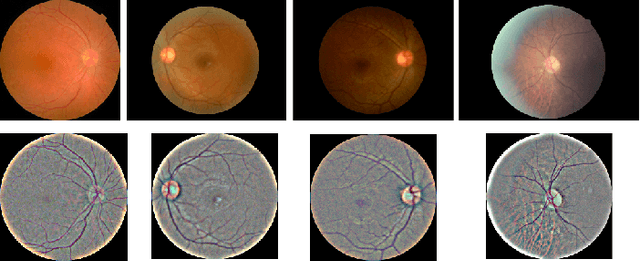

Abstract:Diabetic Retinopathy (DR) is a prevalent illness associated with Diabetes which, if left untreated, can result in irreversible blindness. Deep Learning based systems are gradually being introduced as automated support for clinical diagnosis. Since healthcare has always been an extremely important domain demanding error-free performance, any adversaries could pose a big threat to the applicability of such systems. In this work, we use Universal Adversarial Perturbations (UAPs) to quantify the vulnerability of Medical Deep Neural Networks (DNNs) for detecting DR. To the best of our knowledge, this is the very first attempt that works on attacking complete fine-grained classification of DR images using various UAPs. Also, as a part of this work, we use UAPs to fine-tune the trained models to defend against adversarial samples. We experiment on several models and observe that the performance of such models towards unseen adversarial attacks gets boosted on average by $3.41$ Cohen-kappa value and maximum by $31.92$ Cohen-kappa value. The performance degradation on normal data upon ensembling the fine-tuned models was found to be statistically insignificant using t-test, highlighting the benefits of UAP-based adversarial fine-tuning.